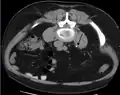

Otherwise a noncontrast helical CT scan with 5 millimeters (0.2 in) sections is the diagnostic method to use to detect kidney stones and confirm the diagnosis of kidney stone disease.[16][56][60][65][7] Near all stones are detectable on CT scans with the exception of those composed of certain drug residues in the urine,[58] such as from indinavir.

Measurement of a 5.6 mm large kidney stone in soft tissue versus skeletal CT window.